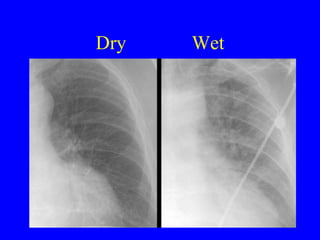

Dry Wet

Airspace Edema May be cardiogenic or non-cardiogenic Very non-specific: aspiration, atypical pna, hemorrhage, etc. ARDS will persist and become coarse over time

Air-space edema